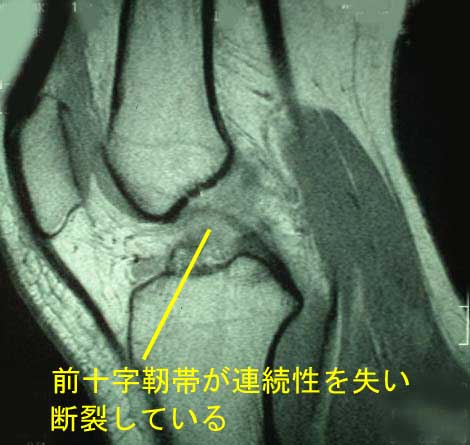

| 膝関節は前後の動揺(ぐらつき)を防ぐために、十字の形をした2本の十字靭帯、すなわち前十字靭帯と後十字靭帯が存在します。前十字靭帯は小指程度の大きさです。後十字靭帯は親指程度の大きさです。前十字靭帯の方が後十字靭帯より強度も弱いため、前十字靭帯の損傷をより多く認めます。 前十字靭帯損傷はバレーボール、バスケットボール、スキー、体操などのスポーツ活動中に発生します。一方、後十字靭帯損傷は強い外力(交通事故、労災事故など)で発生します。また十字靭帯損傷は他の靭帯損傷や半月板損傷を高頻度に合併します。 前十字靭帯損傷 前十字靭帯は大腿に対して下腿が前方に移動する動きを制御しています。したがって前十字靭帯が損傷すると、下腿が大腿に対して前方へ移動することになります。大半はスポーツ中のジャンプの着地時や急な減速や方向転換の際に、膝関節に外反ストレスと下腿の内旋、前方移動が加わって発生します。解剖学的特性より女性に多く、男性の2〜3倍程度と言われています。前十字靭帯断裂の大半は中央部での断裂です。 症状 受傷時に断裂音(ポキッ)を認めると同時に痛みや腫れ、運動障害、歩行障害を訴えます。陳旧例(時間が経過した症例)は関節の不安定性や膝崩れ現象(膝が抜ける感じ)、脱臼感を訴え受診されます。 診察 膝の不安定性の検査(ラックマンテスト、前方引き出しテストなど)が陽性となります。関節が腫れているので穿刺すると関節内血種(関節の中に血液)を認めます。なおスポーツ活動中に起こる関節内血腫は70%程度に前十字靭帯損傷を認めると報告されています。 診断 レントゲン検査で下腿を前方へ引き出すようなストレスをかけると不安定性が確認されます。時に靭帯の付着部で剥離骨折を認めることもあります。診断はMRIです。診断率は90%と言われています。また、内側側副靭帯損傷や半月板損傷を高頻度に合併しています。確定診断は関節鏡です。 治療 保存的治療(手術しない方法)と手術的治療に分かれます。 1)保存的治療 急性期はライスの処置を行います。保存的治療は部分損傷例や小児や高齢者の症例です。軟性サポーターや硬性装具を着用をすすめます。早期より筋力強化訓練を行います。ただし前十字靭帯損傷は自然治癒能力が弱いため成績はあまりよくありません。また将来、半月板損傷や変形性膝関節症の発症を招くことがありますので、保存的治療には限界があります。青壮年やスポーツ愛好家は積極的に手術が行われます。 2)手術的治療 関節鏡視下自家腱再建術(自分の膝周囲の腱である半腱様筋腱や薄筋腱、骨付き膝蓋腱など)を用いた靭帯再建術が検討されます。移植した腱が靭帯化するまで8ヶ月〜1年程度と言われています。スポーツ復帰は1年前後となります。また手術後の再断裂や反対側の断裂の発生を30%程度に認められると報告されています。なお小児の症例では骨端線(成長線)があるため手術の適応に慎重を要します。 後十字靭帯損傷 後十字靭帯は大腿に対して下腿が後方に移動する動きを制御しています。したがって後十字靭帯が損傷すると下腿が大腿に対して後方へ移動することになります。交通事故の際にダッシュボードで下腿前面を強打した際やラブビーなどのスポーツで下腿前面にタックルされた際に前方からの強い外力で損傷します。 症状・診断 打撲した下腿前面の痛みや膝の後面(後十字靭帯の付着部)の痛み、腫れ、運動障害、歩行障害です。陳旧例では関節の不安定性や脱臼感を訴えます。診察では下腿が後方に落ち込み、関節の不安定性検査(後方引き出しテスト)などが陽性となります。関節穿刺すると関節内血腫を認めます。レントゲン検査で下腿を後方へ押し込むストレス撮影で不安定性が確認されます。時に靭帯付着部に剥離骨折を認めることもあります。詳細な情報収集にはMRIやCT、関節鏡が必要です。 治療 保存的治療と手術的治療に分かれますが、後十字靭帯損傷は前十字靭帯損傷に比べて日常生活動作にあまり支障を来たすことはないようです。大半は保存的治療が行われます。安静の目的でギプス包帯や装具療法が行われます。早期より筋力強化訓練を行います。なおスポーツ選手や動揺性(ぐらつき)の激しい症例では後十字靭帯再建術が検討されます。 |